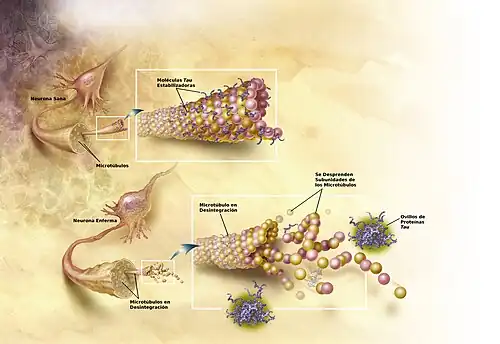

Esta observación apoya la hipótesis tau, la cual defiende que es esta proteína la que da inicio a la cascada de trastornos de la enfermedad de Alzheimer.[57] De acuerdo con este modelo, las tau hiperfosforiladas adoptan formas anómalas, distribuyéndose en largas hileras. Eventualmente forman ovillos de neurofibrillas dentro de los cuerpos de las células nerviosas.[75]

Cuando esto ocurre, los microtúbulos se desintegran, colapsando el sistema de transporte de la neurona. Ello puede dar inicio a las primeras disfunciones en la comunicación bioquímica entre una neurona y la otra y conllevar la muerte de estas células.[76]

La enfermedad de Alzheimer se considera, debido a la agregación anormal de la proteína tau, como una tauopatía. Las neuronas sanas están compuestas por citoesqueleto, una estructura intracelular de soporte, parcialmente hechas de microtúbulos. Estos microtúbulos actúan como rieles que guían los nutrientes y otras moléculas desde el cuerpo neuronal hasta los extremos de los axones y viceversa. Cada proteína tau estabiliza los microtúbulos cuando es fosforilada y por esa asociación se le denomina proteína asociada al microtúbulo. En el alzhéimer, la tau debido a cambios químicos que resultan en su hiperfosforilación, se une con otras hebras tau creando ovillos de neurofibrillas y de esta manera, desintegra el sistema de transporte de la neurona.[89]